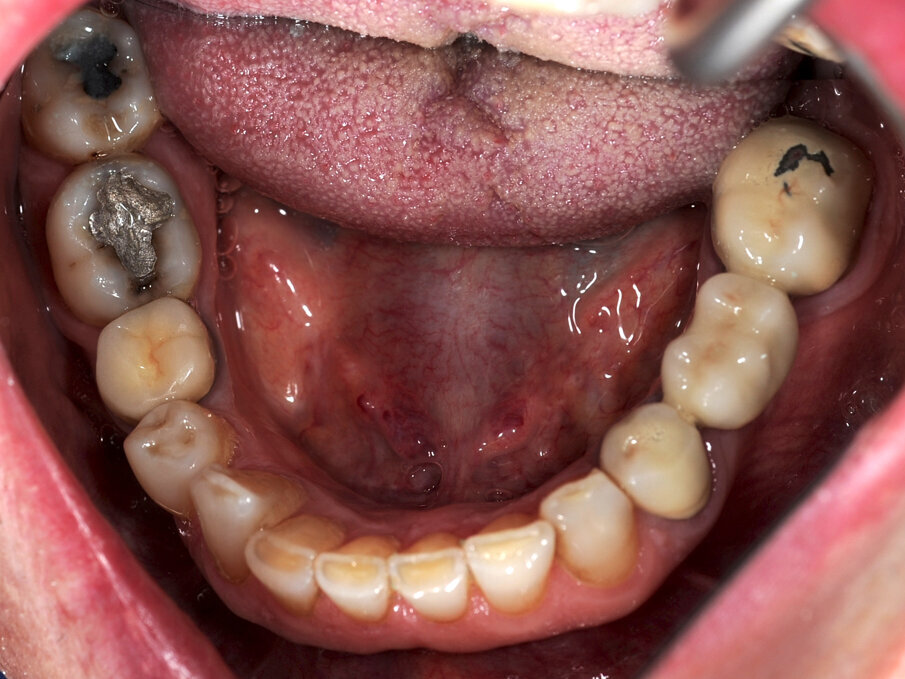

Un paziente di 66 anni, con anamnesi patologica di NIDDM ben compensato e cardio-vasculopatia ischemica in buon compenso farmacologico, si presenta alla nostra attenzione per ascesso parodontale alla radice residua del dente 1.2 e per multiple fratture dei manufatti protesici esistenti (Figg. 1-6). È evidente la presenza di grave malocclusione con perdita di VDO, usure e fratture dei restauri protesici e dei denti residui, presenza di abfractions cervicali. Il paziente evidenzia alla visita modesta dolenzia muscolare alla palpazione, specie a carico dei muscoli pterigoidei mediali e temporali, apertura della bocca ridotta e lieve rumorosità delle TMJ.

L’infezione a carico della radice del dente 1.2 è immediatamente attribuibile a frattura verticale con sondaggio positivo di 9 mm (Fig. 7). Estratta la radice di 1.2 fratturata, il paziente richiede una riabilitazione protesica fissa all’arcata superiore che preveda il minor numero possibile di interventi endodontici e chirurgici. Viene da noi proposta una riabilitazione protesica full arch che consenta, previo studio del caso gnatologico e terapia interlocutoria con provvisori in PMMA, la definizione di un’occlusione a funzione sequenziale in TRP per l’aumento controllato della VDO e la stabilizzazione dei rapporti articolari, ora visibilmente compromessi.